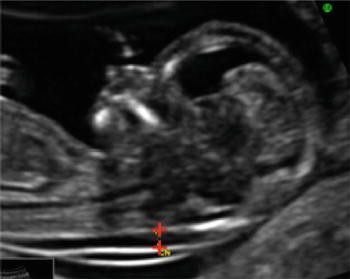

High thickness measurements are also associated with congenital heart defect . [1] The scan is carried out at 11-13 .6 weeks pregnancy and assesses the amount of fluid behind the neck of the fetus - also known as the nuchal fold or 'the nuchal translucency' . Fetuses at risk of Down tend to have a higher amount of fluid around the neck .

A nuchal scan or nuchal translucency (NT) scan/procedure is a sonographic prenatal screening scan to detect chromosomal abnormalities in a fetus, though altered extracellular matrix composition and limited lymphatic drainage can also be detected . . Since chromosomal abnormalities can result in impaired cardiovascular development, a nuchal translucency scan is used as a screening, rather than . . .

In the majority of fetuses with trisomy 21, the nuchal translucency thickness was <4 .5 mm, while with trisomies 13 or 18 it was 4 .5-8 .4 mm, and in those with Turner syndrome it was 8 .5 mm or more 9 . Correlation with serum markers

Figure 2 . Increased nuchal translucency thickness (NT) The findings of numerous studies suggest that an effective first trimester screening for trisomy 21 can be obtained by the combination of maternal age and measurement of fetal NT [4-11] .At a risk cut-off of 1 in100, the detection rate of trisomy 21 is about 75%, at a false positive rate of about 2% .

ultrasonography as increased nuchal translucency in the third month of intrauterine life . Fetal nuchal translucency thickness at the 11-13+6 weeks scan has been combined with maternal age to provide an effective method of screening for trisomy 21; for an invasive testing rate of 5%, about 75% of trisomic pregnancies can be identified .